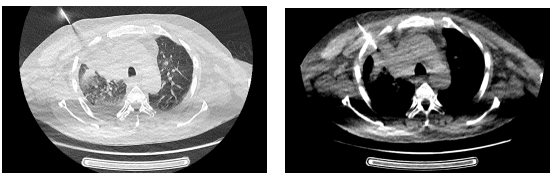

为确保手术的成功与安全,阿坝州人民医院运用多学科协作优势。外二科杜刚主任医师制定了详细的术中、术后并发症处理预案,为手术的成功提供了坚实的保障。放射科蒲鹏主任医师用经验和技术,为手术制定了精确的穿刺进针路线。在唐大东主任医师的精细操作下,整个穿刺过程仅用了约30分钟便顺利完成,且患者未出现明显的出血、气胸等并发症。

在穿刺过程中,医生们通过实时监测CT影像,不断调整穿刺针的位置和角度,以确保穿刺的准确性和安全性。

CT引导下经皮肺穿刺活检术的成功开展,为患者提供了更为精准、安全的诊断手段,标志着阿坝州人民医院在肺部疾病诊断领域迈上新的台阶。这一技术的引入和应用,将有助于提高肺部疾病的诊断准确率,减少误诊和漏诊的发生,为患者制定更为合理、有效的治疗方案提供有力支持,为更多肺部疾病患者带来福音。